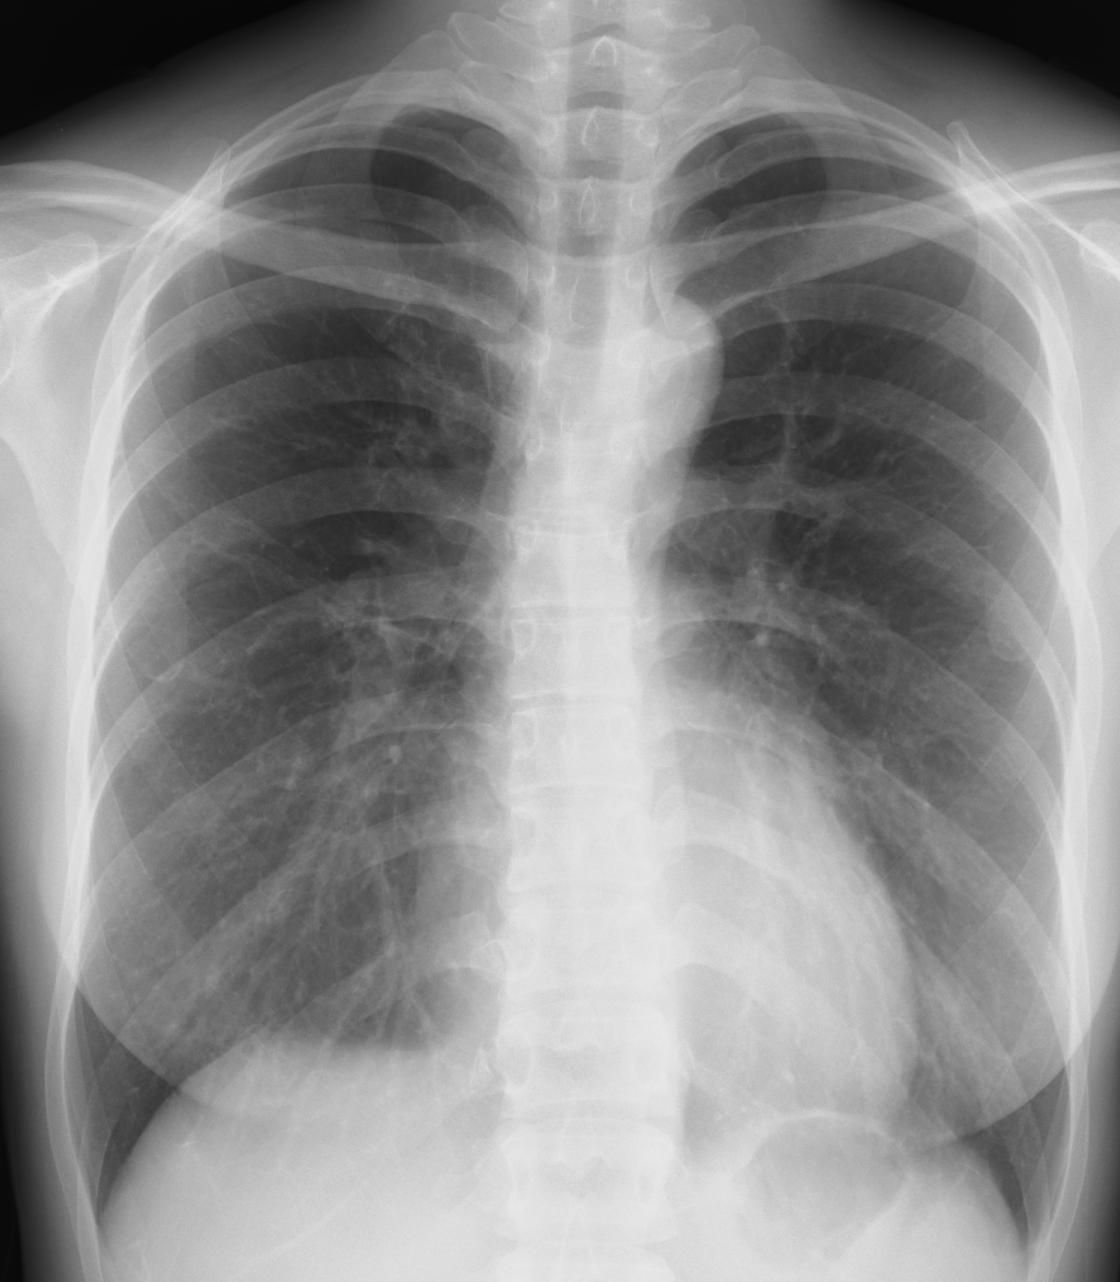

外来でよくみられる肺炎、マイコ・クラミジア・肺炎球菌・ウイルス(RSウイルス・hMPV・インフルエンザウイルスA・B)について実際に経験、外来で治癒した症例を提示します。軽症な変化のものが大多数ですが中には重症なものも紛れていて、注意が必要になります。

【マイコプラズマ肺炎】